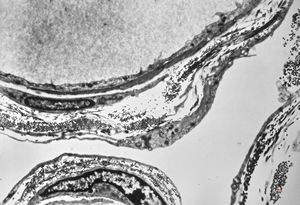

M,6y. | the wall of an arachnoid cyst

F,11y. | the wall of the arachnoid cyst

F,47y. | arachnoid cyst

F,25y. | arachnoid cyst

F,13y. | arachnoid cyst

M,6y. | the wall of an arachnoid cyst